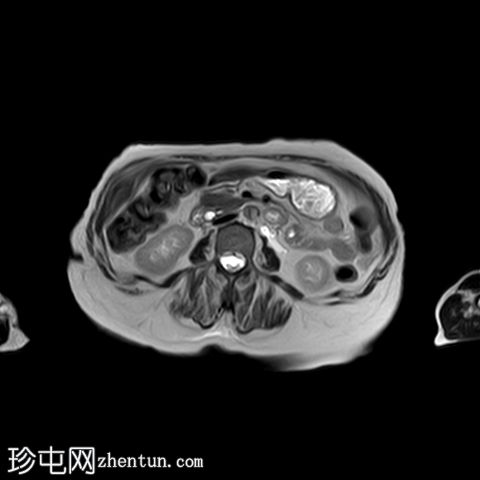

轴位

DWI

5.jpg

子宫呈U形,宫底轮廓消失,宫底突出至扩张的阴道内,宫颈位于内翻的宫底上方(II级子宫内翻):

宫底处可见阴道内可见边界不清、分叶状实性肿块,明显扩张阴道壁,阴道壁完整。

肿块最大轴向及头尾径约为 9.7 x 9.6 x 9.5 cm,T1 加权像呈低信号,T2 加权像呈中/高信号,伴有扩散受限和不均匀增强。

肿块前方压迫膀胱,后方紧邻乙状结肠,未见侵犯。

肿块压迫左侧远端输尿管,导致轻度输尿管肾积水。

MRI有助于确定病因,尤其是在非产褥期病例中(例如,子宫肌瘤、子宫肌肉瘤或子宫内膜恶性肿瘤),如本例所示。